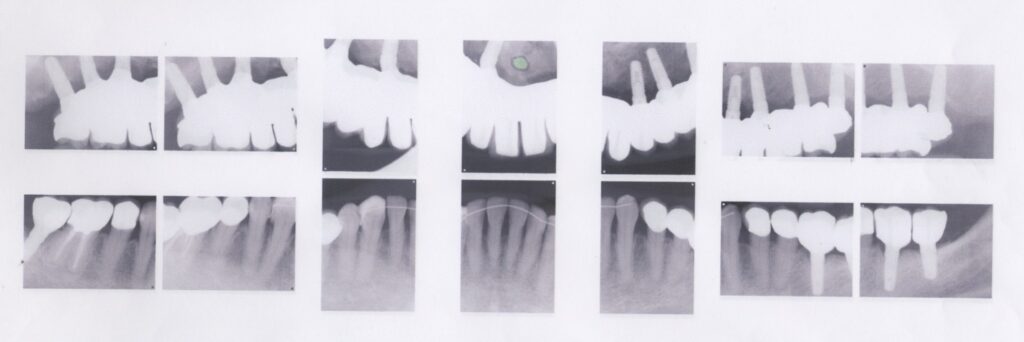

- 10年前から他の歯科医院にて入れ歯治療を受けたが、見た目が良くない・噛めないと・喋りにくいとのことで再治療を希望された。アングルクラスⅢであった。左右上奥歯がない。

- 上顎左右側にインプラントを8本し、

- 入れ歯+オールセラミックのボーンアンカーブリッジにて被せ物を行なった。

- 下顎臼歯に3本のインプラントを入れ、オールセラミッククランにて被せ物を行なった。

治療結果

- 審美的な仕上がりで、患者自身も満足した。9年経過し良好である。

現在は2〜3ヶ月おきのメインテナンス中である。